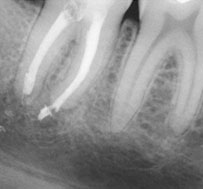

Breakage of endodontic files during treatment can result in serious complications and jeopardize the outcome of treatment. When using nickel-titanium (Ni-Ti) files, prevention of file breakage is complicated by the fact that these files rarely demonstrate visible evidence of cyclic fatigue and torsional stress and do not show wear before breakage.1 In the event that a file does break, removal can be difficult due to anatomical considerations, and the long-term prognosis of the tooth can become guarded.

An unfinished root canal will eventually cause many problems. The most common complication is that the tooth will begin to cause pain. There is also a risk that the tooth may fracture or cause a potentially dangerous swelling of the gum.

The greater the amount of uncleaned and unfilled canal space that remains after a root canal procedure, the greater failure rate. The challenge for clinicians is to decide to what point endodontic obturation should be directed in the given procedure. Cleaning, shaping and obturating less than the entire root canal space has the potential to or certainly could leave uncleaned and unfilled space, especially if the root is obturated to levels determined by arbitrary anatomic averages and not the true apical foramen.

Root canal overfills occur when a dentist is obturating (filling) a root canal. If the gutta percha(canal filling material) extrudes out the end of the root it is called an overfill. Sometimes, the gutta percha may have slipped through because it was not of sufficient diameter to bind at the apex. If a guttapercha that is too small is used, it can slip thru the tiny apical foramen (a hole at the tip of the root) and the resulting over fill may or may not form good seal . If the gutta percha does not adequately obturate (seal) the apex, then bacteria can repopulate any left over space. This bacterial colonization is most likely the actual cause of most endodontic failures associated with overfills.